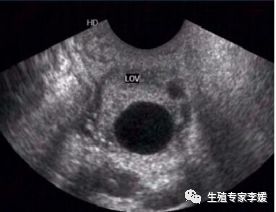

四、 超声监测

超声监测排卵一般从月经周期第8-10天开始,通过超声监测卵泡由小到大并且最终排出的过程,期间结合抽血及验尿结果综合评估,一个周期如果顺利需要3-5次监测。

优点:最精确,最全面,可以检测到卵泡是否正常排出

缺点:必须在在专业门诊完成,需要反复多次去医院,比较繁琐,花费相较其他方法高。